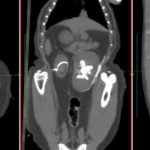

急性腎機能障害の猫ちゃんが(BUN>130mg/dl、Cre>14mg/dl、高カリウム血症)治療のため救急で対応しました。無麻酔CTでは両側に尿管結石が確認されました。著しく拡張している左腎の腎盂に一時的な腎瘻カテーテルを設置し、尿の排泄路の確保を行います。しかし、腎数値に改善は見られませんでした。腎盂造影を行うと拡張している腎臓において尿の産生と排泄は行われている様です。一方、腎盂拡張のほとんどない右腎の腎盂造影では尿の排泄が確認されません。今回の急性腎機能障害の原因は機能の残っていた右腎の急性尿管閉塞による急性腎障害と診断しました。左腎に関しては尿の産生はあるものの慢性腎機能障害であり、すでに尿濃縮能は失われていると判断しました。右腎の問題に対して尿管膀新吻合短尺型ステント設置術を行いました。術後は徐々に腎数値は低下し、腎機能の回復が得られました。一見すると腎盂拡張の顕著な側が急性腎障害の責任病変と判断しがちですが、片腎が十分に機能していれば腎数値に影響はほとんどなく、どちらの腎臓を治療対象とするか?エコー、CTなどの画像診断、血液検査、一時的な腎瘻カテーテルの設置、腎盂造影など総合的な判断が必要です。また判断がつかず、左右同時に治療が必要な場合もあります。